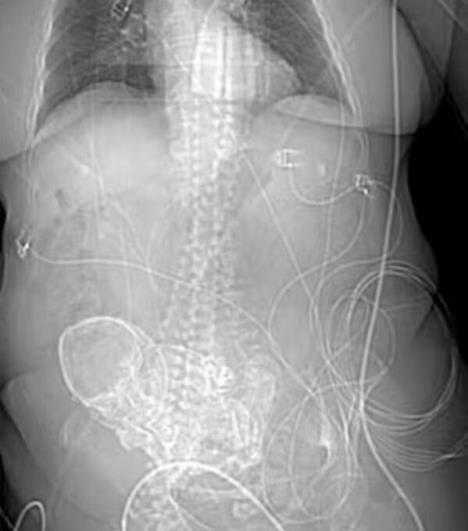

Sledećeg dana dobila je uput za dodatno lečenje u regionalnu bolnicu gde joj je 3D snimanje dijagnostikovalo litopediju, retku nuspojavu vanmaterične trudnoće.

Pošto je fetus umro tokom Verine trudnoće, njeno telo ga nije apsorbovalo. Umesto toga, zadržan je u trbušnoj duplji i preko njega se formira kalcijumska školjka.

Prema Nacionalnom institutu za zdravlje, većina ovakvih stanja je asimptomatska i stanje se otkriva kada se naruče rendgenski snimci.